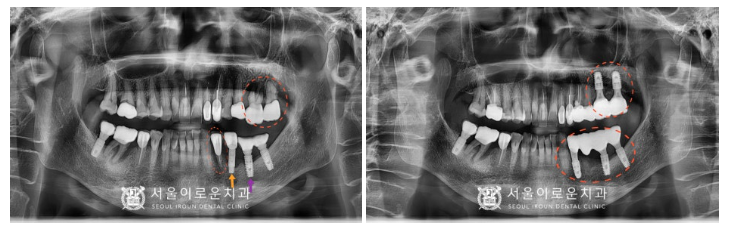

먼저 위턱 왼쪽 어금니 두 개(#26,27) 발치 후

염증을 깨끗하게 제거해주었습니다.

염증이 남아있게 되면

임플란트가 단단하게 고정되지 못하고

추후 금방 탈락하는 등

부작용이 생길 수 있기 때문에

염증조직을 남기지 않고

깨끗하게 제거하는데 집중하였습니다.

염증조직 제거를 마무리하고

임플란트 즉시 식립 후

염증으로 인해 뼈가 흡수된 부분에

뼈이식을 같이 진행하였는데요.

뼈이식 후 차폐막을 대어

이식한 뼈가 빠져나오지 않고

안정적으로 자리 잡아

잘 유지될 수 있도록 해주었답니다.

그리고 아래턱 왼쪽 첫 번째

작은 어금니(#34) 발치와

두 번째 작은 어금니 임플란트(#35) 제거 후

마찬가지로 염증조직을

깨끗하게 제거한 뒤

(#34) 부위에

임플란트 즉시 식립을 진행하였으며,

해당 부위도 위와 마찬가지로

뼈이식 및 차폐막을 활용하여

수술을 진행했습니다.

또한 첫 번째 어금니 기존 임플란트(#36)는

치은박리소파술로

염증 제거를 도와드렸습니다.